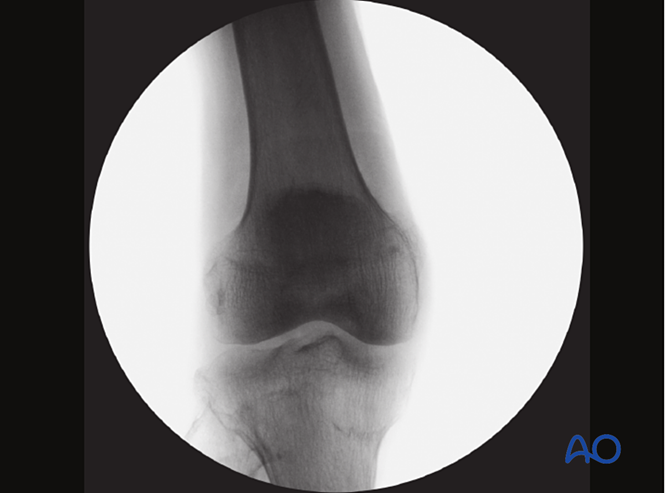

使用影像增强器在前后位和侧位视图中检查复位情况。

●在影像增强器视图上观察骨折线。识别因骨折块重叠而产生的间隙或密度增加区域。●在前后位视图上沿内侧皮质线观察,在轴位视图上沿前侧皮质线观察。识别任何平移或成角畸形。满意的复位质量应呈现以下特征:骨折线沿线无间隙或密度增加;在前后位视图中:●内侧皮质线连续;●无内翻成角;●在侧位视图中:●前倾角约为15°;●前侧皮质线连续。更多细节,请参见关于复位质量评估的附加材料:转子间骨折术中如何评估复位质量?